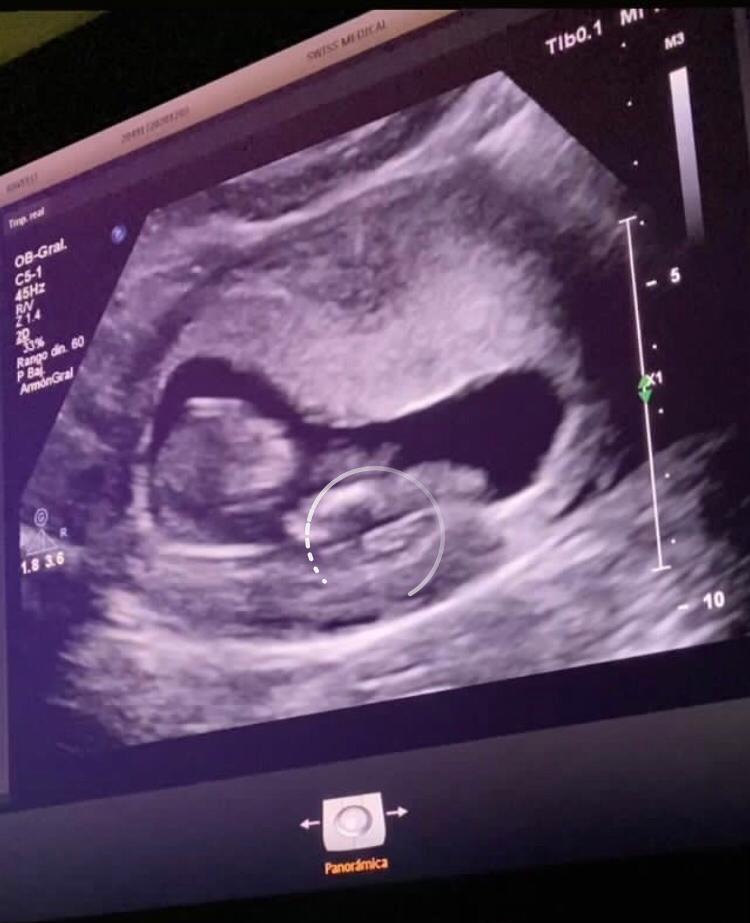

Para confirmar la noticia, hoy Sabrina compartió en sus stories un video de su primera eco y dejó indicios que espera una nena.